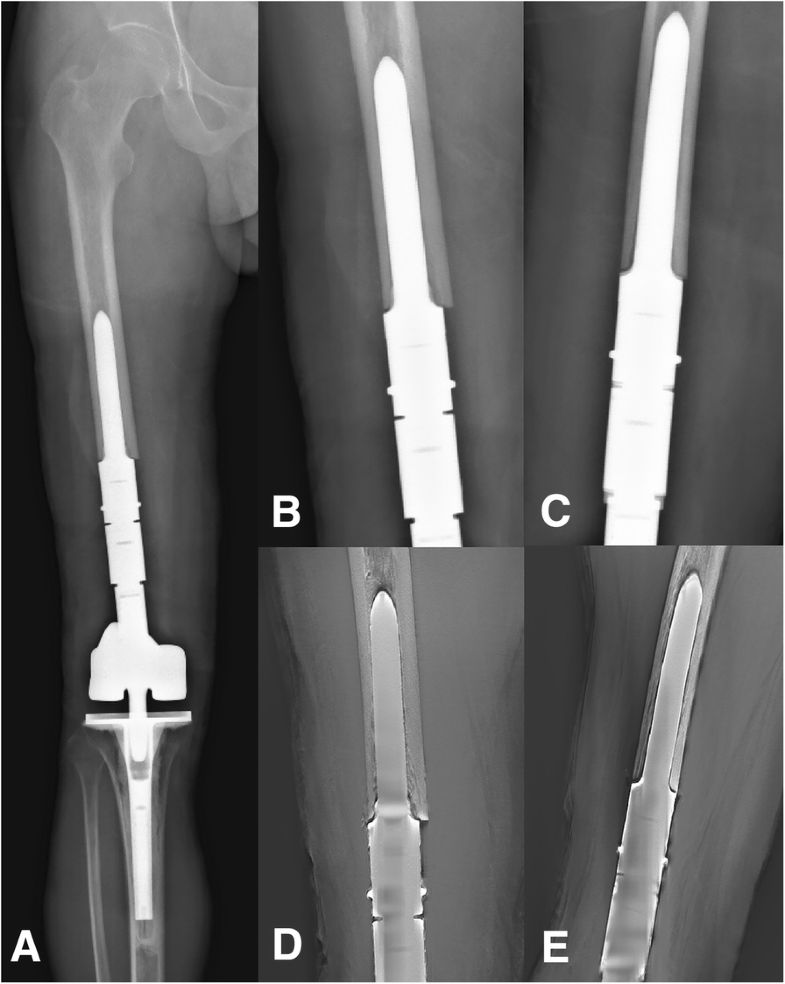

From wjso.biomedcentral.com

Uncemented, curved, short endoprosthesis stem for distal femoral Stem Of Femur the shaft of the femur descends in a slight medial direction. Even if the benefits of collars are unclear, they remain widely used, in several femoral. femoral stem cementation provides excellent implant longevity with a low periprosthetic fracture rate among. basic science of cemented femoral stem fixation. A comprehensive comparison of the performance of different femoral stem. Stem Of Femur.

From mednexus.org

Fracture of Extensively PorousCoated Cylindrical Femoral Stem Stem Of Femur This brings the knees closer to the body’s centre of. A comprehensive comparison of the performance of different femoral stem geometries in total hip. Vertical height), 3) restore femoral anteversion (average 15 degrees). femoral stem cementation provides excellent implant longevity with. femoral stem cementation provides excellent implant longevity with a low periprosthetic fracture rate among. the femur. Stem Of Femur.

From www.wjgnet.com

Use of short stems in revision of standard femoral stem A case report Stem Of Femur A comprehensive comparison of the performance of different femoral stem geometries in total hip. the femur bone is the strongest and longest bone in the body, occupying the space of the lower limb,. femoral stem cementation provides excellent implant longevity with. Even if the benefits of collars are unclear, they remain widely used, in several femoral. Goals of. Stem Of Femur.

From www.caseclips.com

Periprosthetic Femur Fracture ORIF, Stem Revision Stem Of Femur Goals of stem placement are to 1) restore medial offset, 2) restore leg length (read: This brings the knees closer to the body’s centre of. femoral stem cementation provides excellent implant longevity with. A comprehensive comparison of the performance of different femoral stem geometries in total hip. femoral stem cementation provides excellent implant longevity with a low periprosthetic. Stem Of Femur.